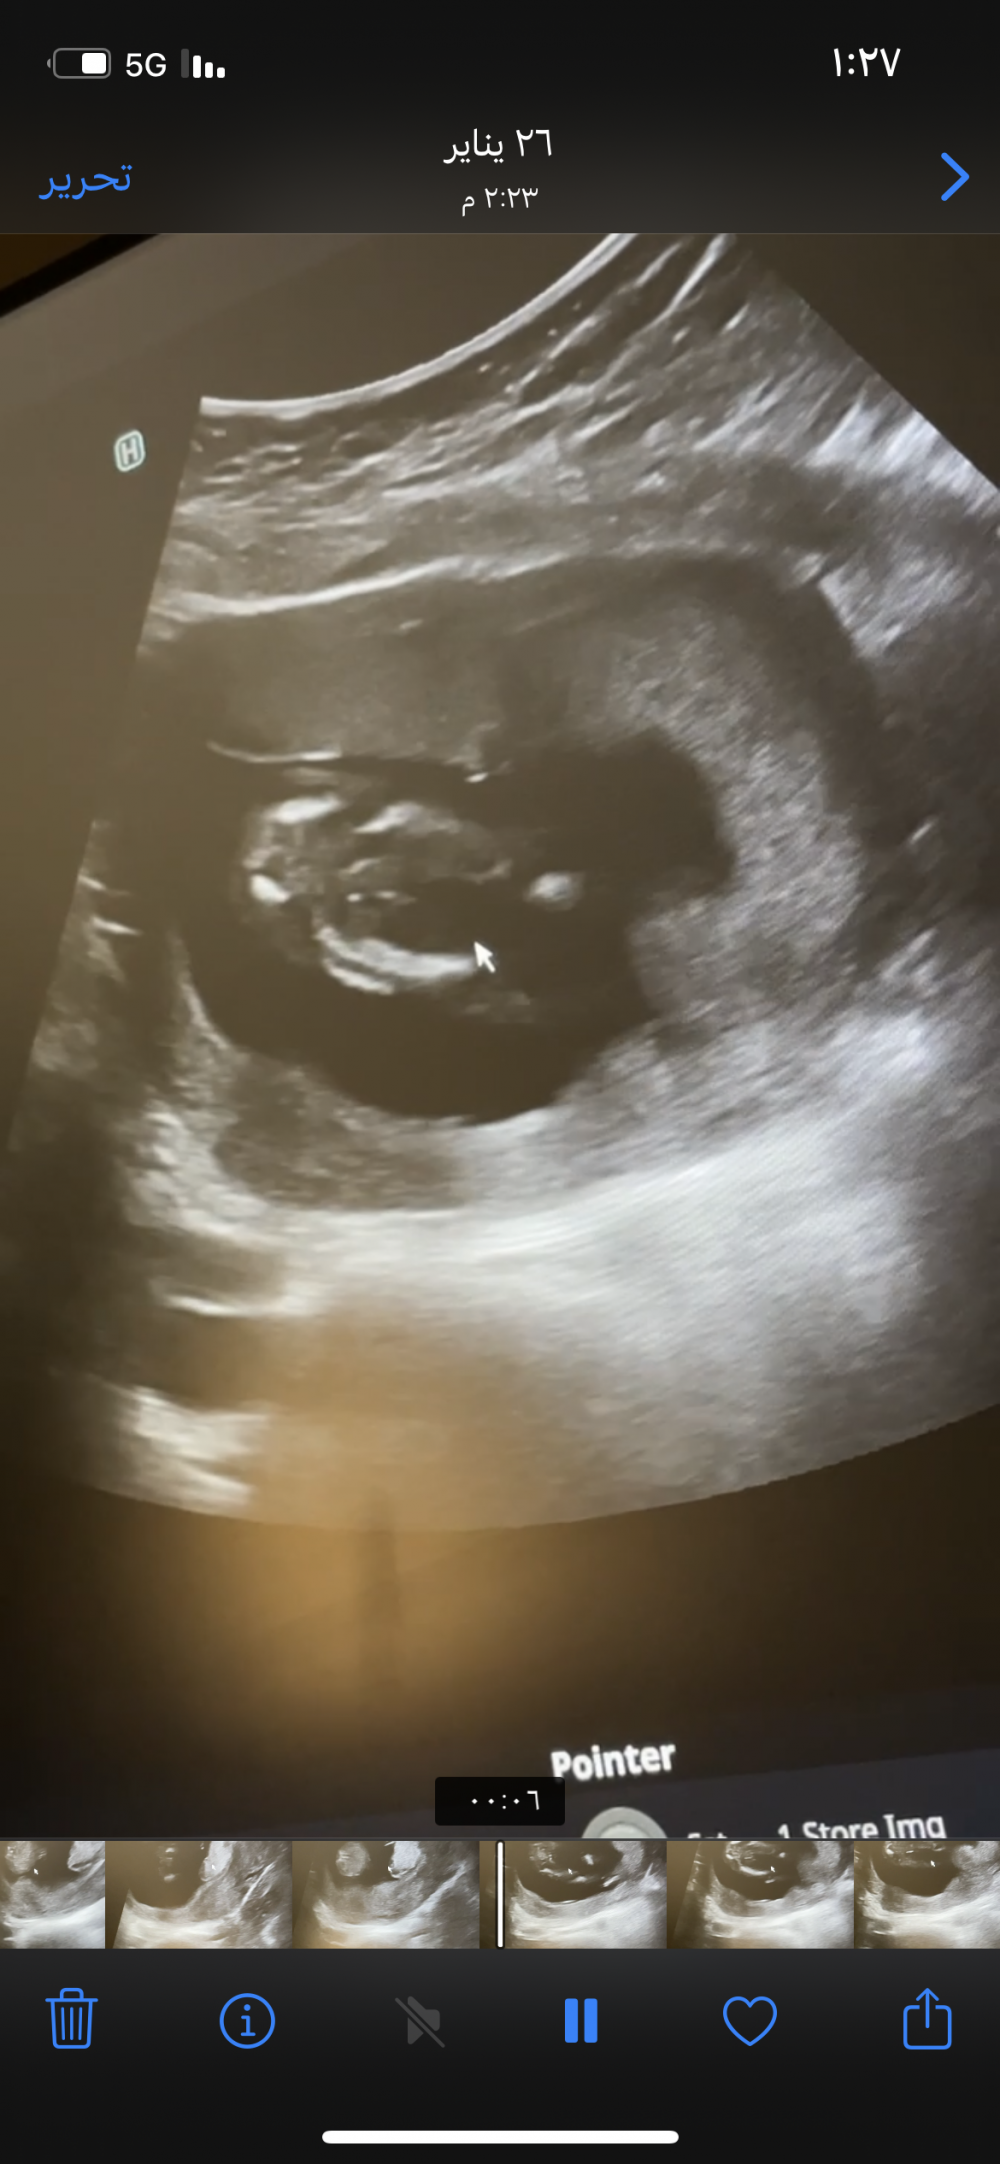

هذا سوناري القديم

بالاسبوع ال١٥ قالولي ولد

والحين بالاسبوع ال٢١

لا رحت للدكتوره الهام بمستوصف الفرايضي قريت عنها مدح وتعرف لجنس الجنين من بدري